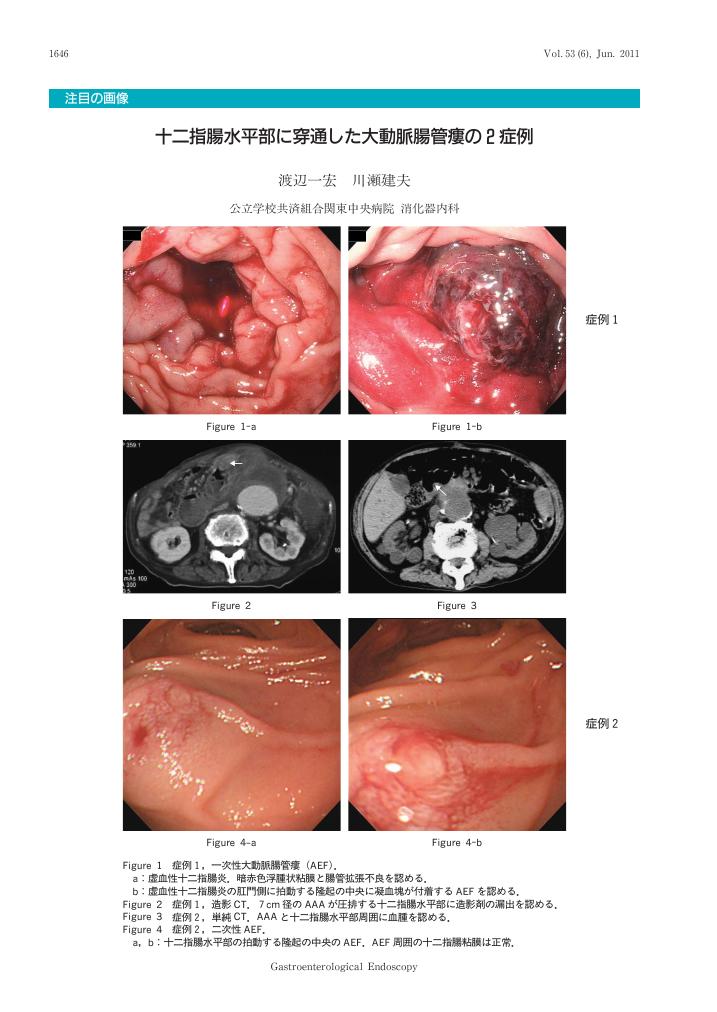

[title in Japanese]